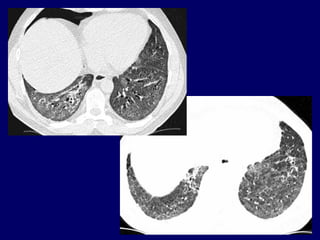

Pulmonary fibrosis and rheumatoid arthritis.

Pulmonary fibrosis andrheumatoid arthritis.